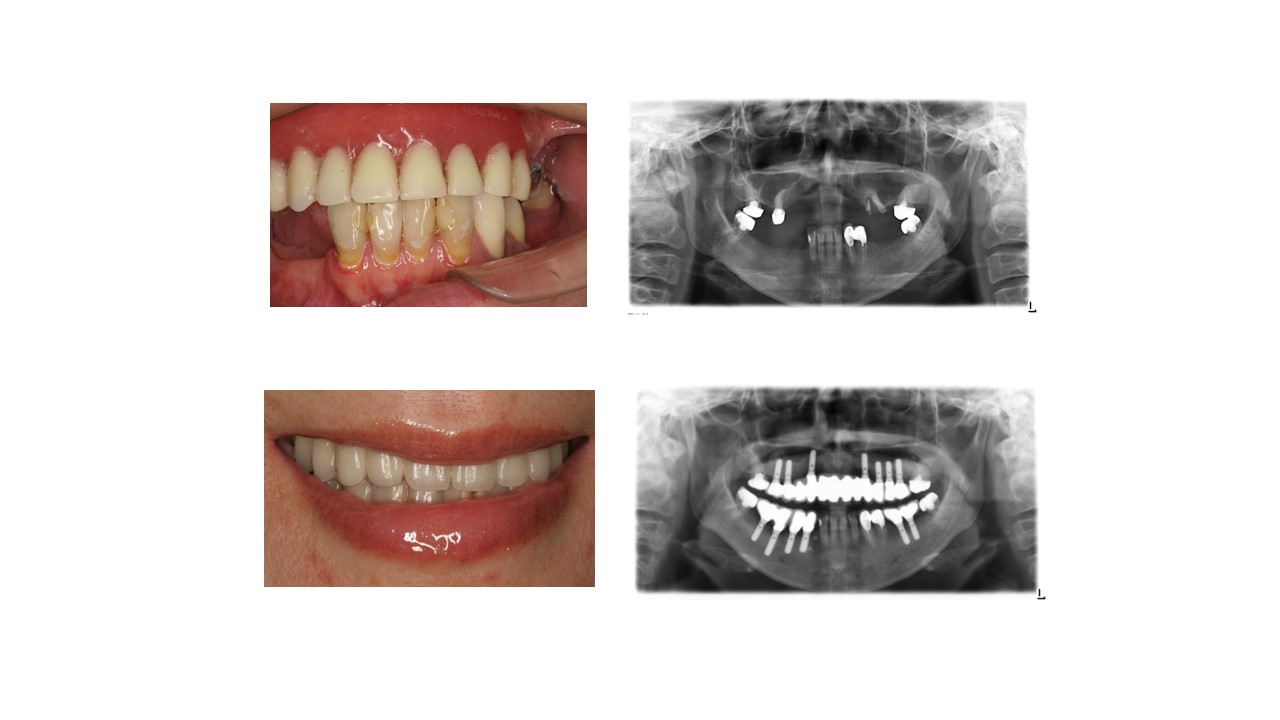

种植科普

幸福的晚年需要健康的牙齿